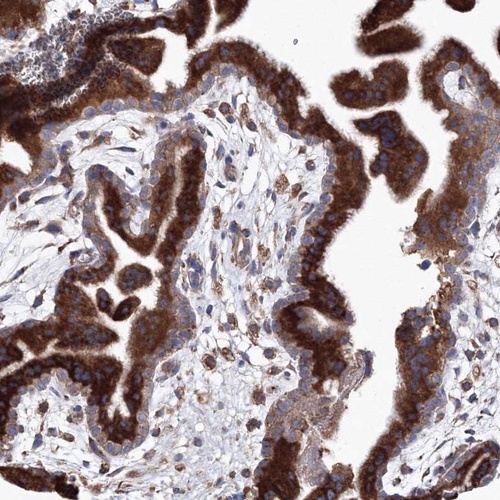

Immunohistochemical staining of human placenta shows strong cytoplasmic positivity in trophoblastic cells.